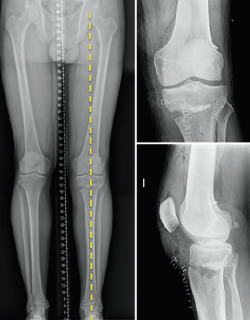

Other diagnostic tests are radiographs under stress varus conditions. We can find indirect radiological signs such as Segond fracture and the arcuate sign. MRI is of great help. Gelber et al. recently reported that over 80% of a group of world experts in the treatment of posterolateral angle injuries agree on the usefulness of MRI in the diagnosis of these lesions(17). Lastly, arthroscopy can offer additional information in the surgical cases (Figure 2).

Figure 2. Arthroscopic view through the anterolateral port of damage to the meniscus-popliteal ligaments (*) at the level of the popliteal hiatus, leaving the tibia exposed (T). P: tendon of the popliteus muscle. Right knee.